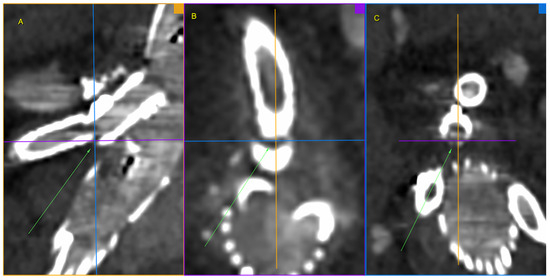

Figure 3. Ruptured superior mesenteric artery branch of stent graft in three planes. The fractured site is centrally located at the intersection of the lines defining the planes and additionally marked with green arrows. Panel (A)—sagittal projection, panel (B)—axial projection, panel (C)—coronal projection. Pre-interventional Angio-CT 3D MPR, arterial phase.

Figure 4. Ruptured superior mesenteric artery branch of stent-graft—the angle between the BeGraft and the vessel. The figure shows a divergence between the axis of the branch and the axis of the superior mesenteric artery. Panel (A)—sagittal projection, panel (B)—sagittal projection with marked angle, panel (C)—axial projection with marked angle. Pre-interventional Angio-CT scans, arterial phase.